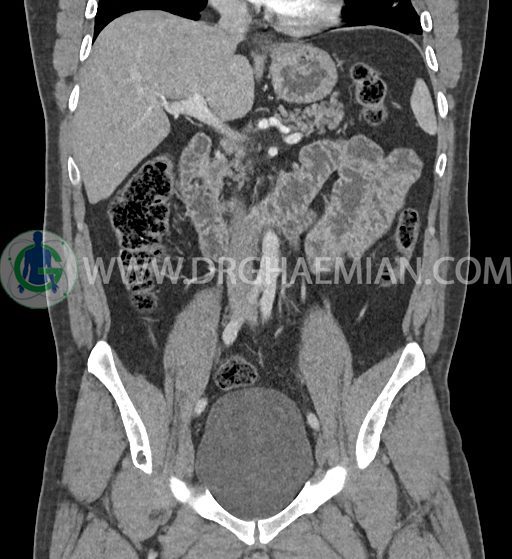

در سی تی اسکن اسپیرال شکم و لگن با کنتراست خوراکی و وریدی (مولتی دیدکتور 16 با مقاطع ظریف و بازسازی های ساژیتال و کرونال) :

-sliding hiatal hernia به ابعاد 60x44mm با جابجایی JE.junction و فوندوس معده به فضای مدیاستن خلفی دیده می شود.